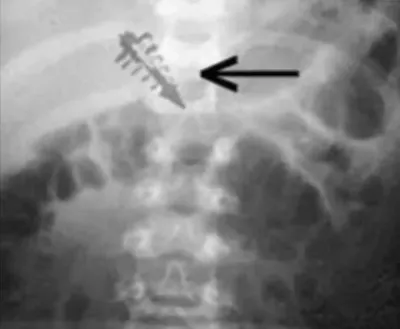

Međutim, pacijenti dr. Leira su na rendgenskim snimcima jasno pokazivali prisustvo stranog metalnog tijela, dok je njihova koža iznad tog mjesta bila potpuno netaknuta.

Magnetizam i radio frekvencije: Prema izvještajima, neki od predmeta su pokazivali snažna magnetska polja (preko 10 gausa) prije nego što su uklonjeni.

Još fascinantnije je to što su neki emitovali radio frekvencije u FM opsegu (npr. 14.7 MHz ili gigahertz frekvencije), što sugeriše da su ovi uređaji aktivno slali ili primali signale dok su bili u pacijentu.